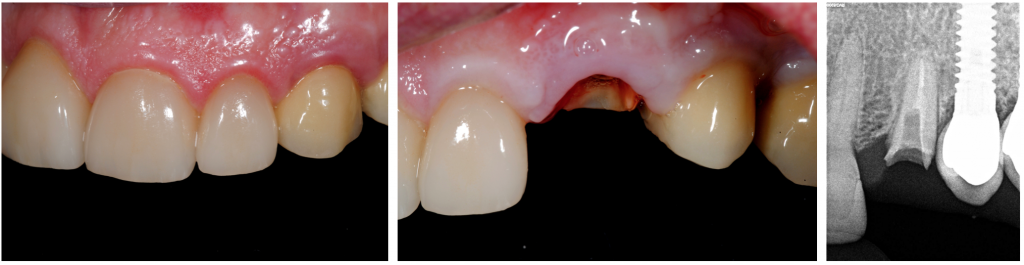

Paciente masculino de 65 años, con rehabilitación fija en el #23 y rehabilitación implantosoportada en los dientes 24 y 25, presentó fractura complicada en el canino izquierdo (#23).

Una extracción conservadora del diente n.º 23 con la posterior reabsorción prevista de los tejidos bucales habría significado un cambio estético de gran alcance. Por tanto, el plan de tratamiento implicaba la colocación inmediata del implante en el sentido delsocket-shield técnica y colocación de implante sin colgajo en el sitio del diente n.º 23 para mantener la arquitectura gingival inicial.

La extracción conservadora del fragmento de la raíz palatina se realizó con unas pinzas especiales, y el alvéolo se desbridó suavemente y se irrigó con solución salina normal.

Se realizó la preparación del lecho del implante en la pared palatina del alvéolo y se colocó un implante en forma de raíz (Klockner ®KL (4,2x12 mm)) según las recomendaciones del fabricante sin contacto con el escudo.

La posición apicocoronal de la plataforma del implante era 1 mm apical a la encía marginal palatina. Se dejó el espacio entre el escudo y la superficie del implante para permitir la formación de coágulos de sangre.

El torque final fue de 50nm, y se optó por hacer carga inmediata no funcional mediante la ferulización del provisional al implante de los dientes 24.